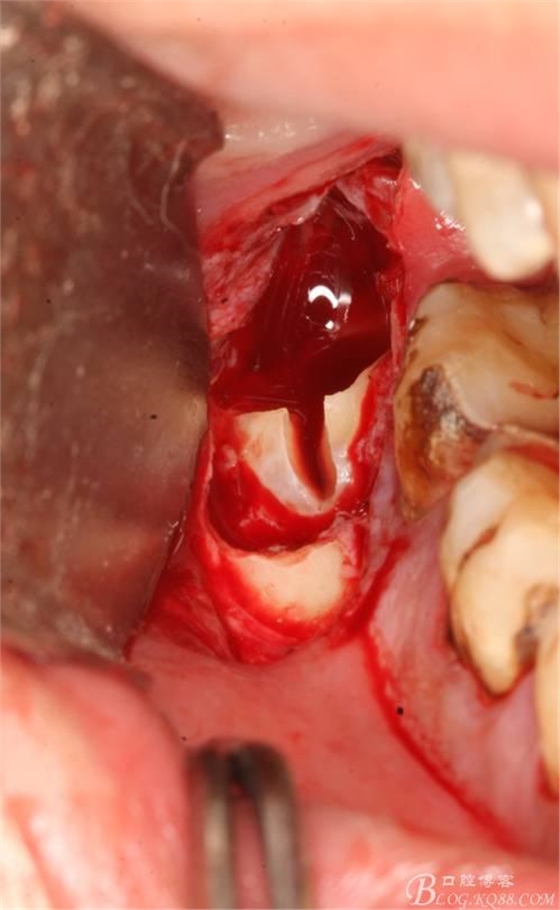

5.取出牙根

6.橫斷牙冠